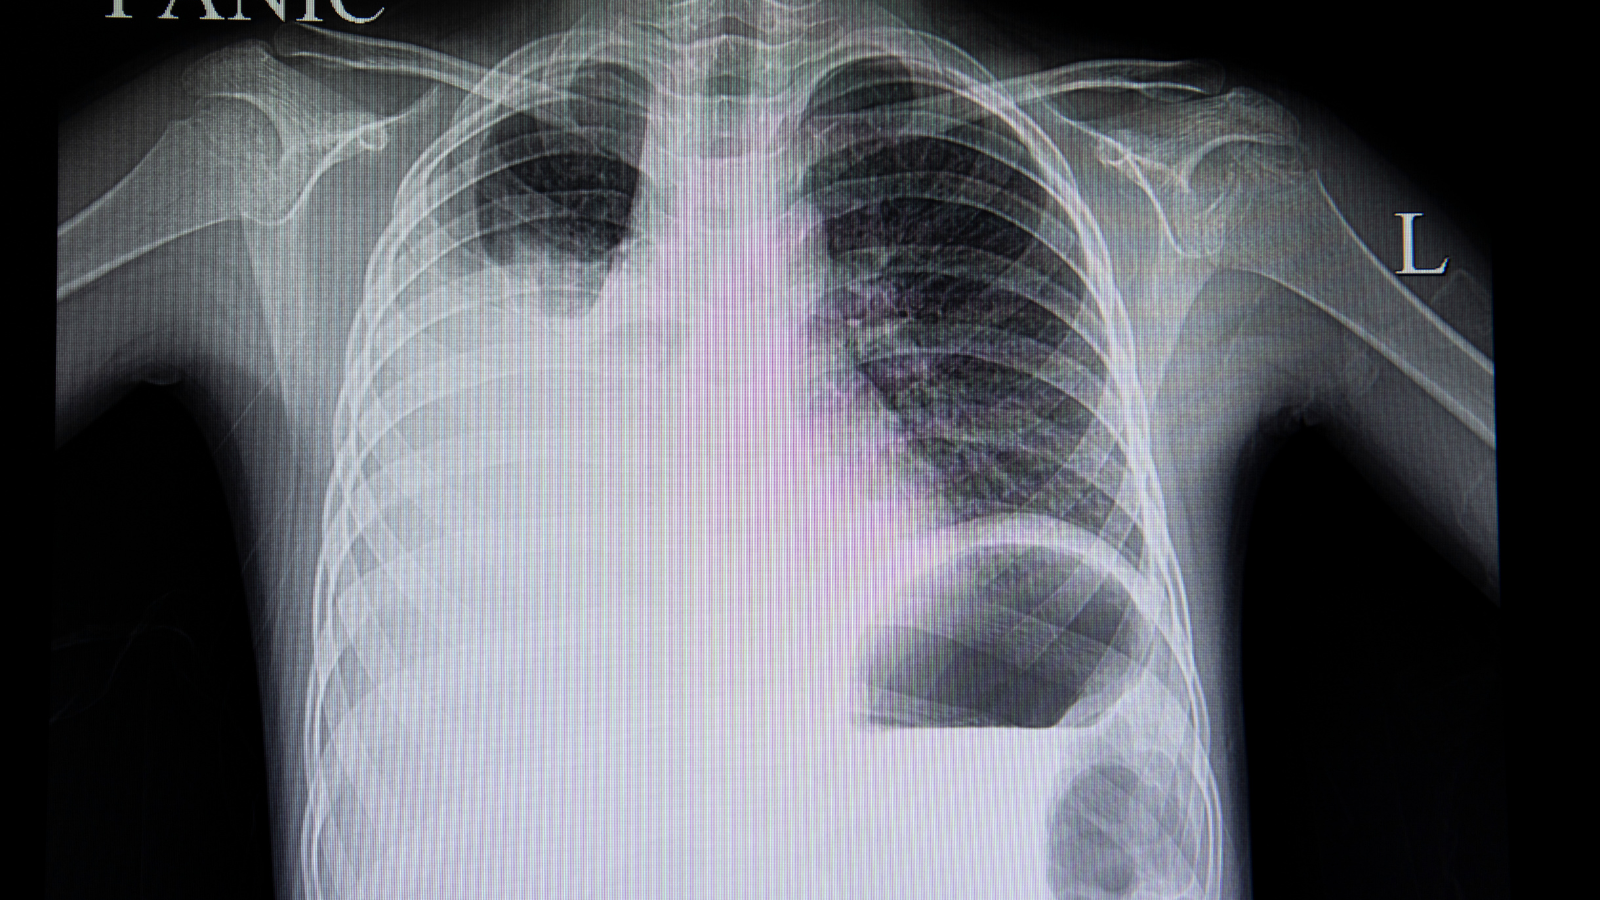

Giữa phổi và thành ngực có một khoảng trống mỏng, gọi là khoang màng phổi. Trong khoang này luôn có một lượng nhỏ dịch giúp bôi trơn và giảm ma sát khi phổi giãn nở, co lại lúc hít thở.

Tràn dịch màng phổi xảy ra khi lượng dịch trong khoang này tăng cao hơn bình thường. Nếu dịch chỉ tăng nhẹ, người bệnh có thể chỉ cảm thấy hơi khó thở hoặc nặng ngực nhẹ. Tuy nhiên, khi dịch tích tụ nhiều, phổi sẽ bị chèn ép, gây khó thở dữ dội, đau ngực, thậm chí đe dọa tính mạng.

Khi dịch trong màng phổi tăng lên, phổi bị chèn ép và không thể giãn nở bình thường. Điều này khiến oxy trong máu giảm, gây khó thở, mệt mỏi, nhất là khi vận động mạnh.